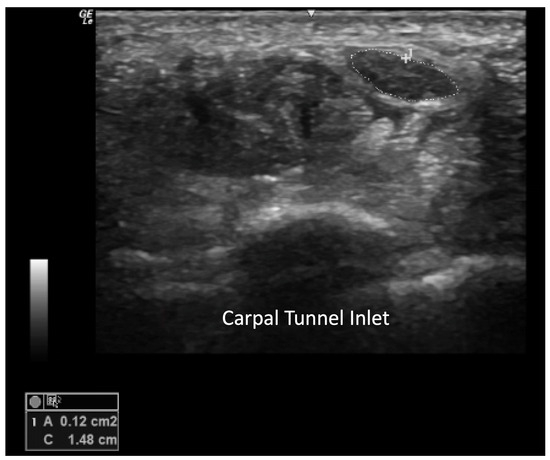

Carpal Tunnel Syndrome

- Yoshii, Y.; Zhao, C.; Amadio, P.C. Recent Advances in Ultrasound Diagnosis of Carpal Tunnel Syndrome. Diagnostics 2020, 10, 596. [Google Scholar] [CrossRef] [PubMed]

- Ziswiler, H.R.; Reichenbach, S.; Vögelin, E.; Bachmann, L.M.; Villiger, P.M.; Jüni, P. Diagnostic value of sonography in patients with suspected carpal tunnel syndrome: A prospective study. Arthritis Rheum. 2005, 52, 304–311. [Google Scholar] [CrossRef] [PubMed]

- Hobson-Webb, L.D.; Massey, J.M.; Juel, V.C.; Sanders, D.B. The ultrasonographic wrist-to-forearm median nerve area ratio in carpal tunnel syndrome. Clin. Neurophysiol. 2008, 119, 1353–1357. [Google Scholar] [CrossRef] [PubMed]